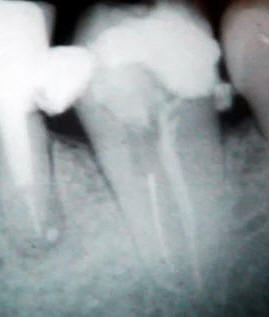

una excelente visión del cabo fracturado

por medio del microscopio dental.

Con una punta de utrasonido para

endodoncia se realiza una guía alrededor del instrumento

fracturado, usando alternativamente lavajes de

Hipoclorito, solución salina y EDTA

Con punta de ultrasonido se elimina el

cabo fracturado.